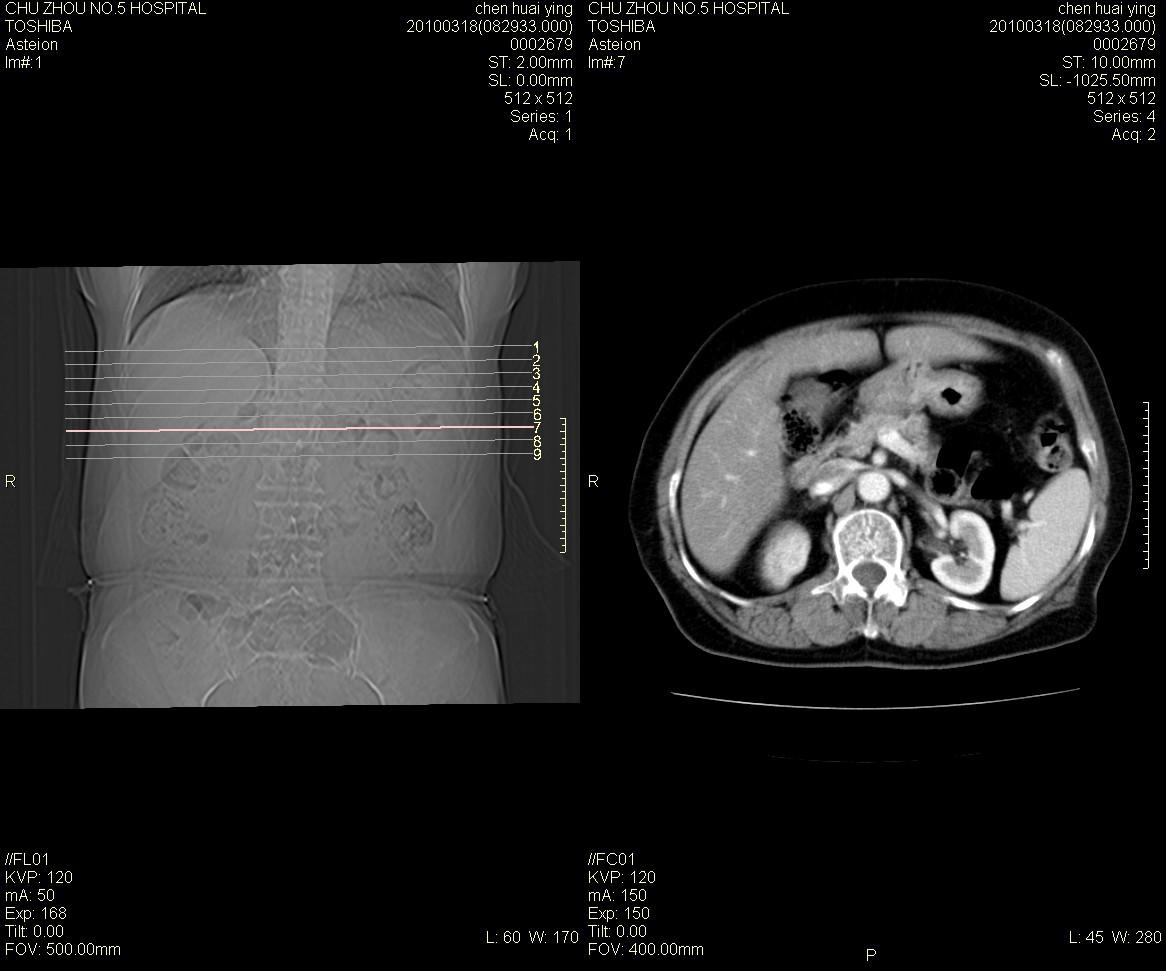

标题: CT25148 肾上腺增强

ct25148增强图片

动脉期太早了,扫的有点低。考虑良性占位右侧肾上腺嗜铬细胞瘤并坏死囊变可能性大,神经鞘瘤不排除。

右侧肾上腺嗜铬细胞瘤并坏死囊变可能性大

考虑双侧肾上腺肿瘤性病变。